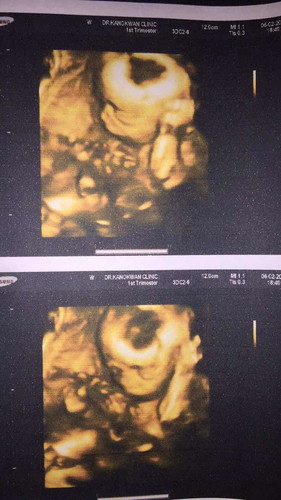

รูปอัลตราซาวด์

รูปแสงตรงว่างๆในภาพอัลตราซาวด์น่าจะเกิดจากมุมแสง รึศีรษะน้องผิดปกติคะ

คุณหมอว่ายังไงคะแม่ ถ้าหากการฝากครรภ์ที่ผ่านมาเป็นปกติ คุณหมอไม่ได้ทักท้วงเรื่องศรีษะน้องแต่อย่างใดคุณแม่สบายใจได้ค่ะ